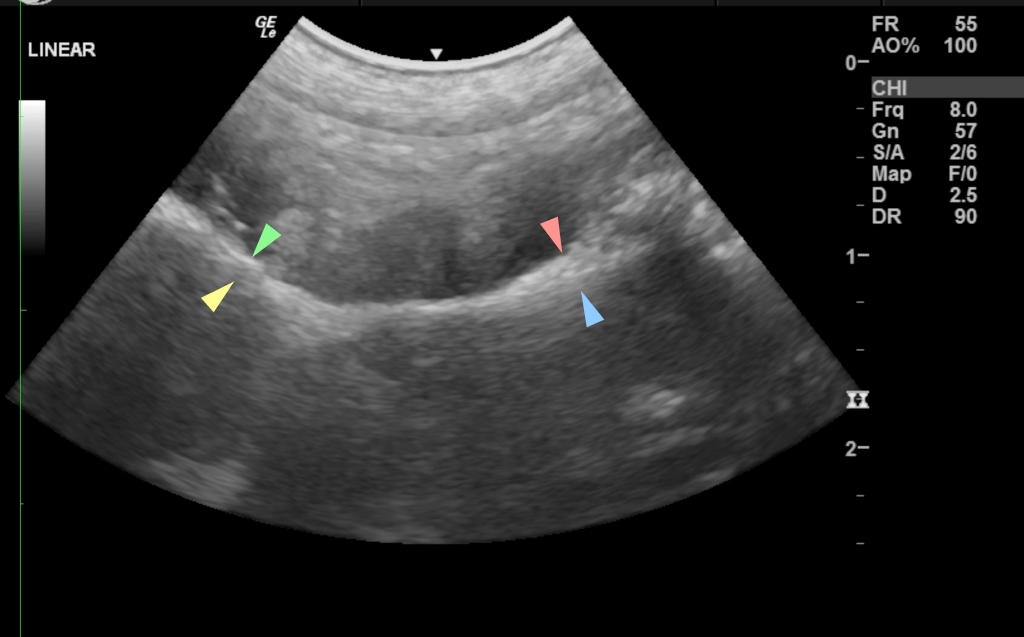

“We immediately carried out blood tests, began intravenous fluid administration and our diagnostic imaging specialist Dr Ian Jones performed an abdominal ultrasound, which confirmed the presence of a gastric and intestinal linear foreign body.